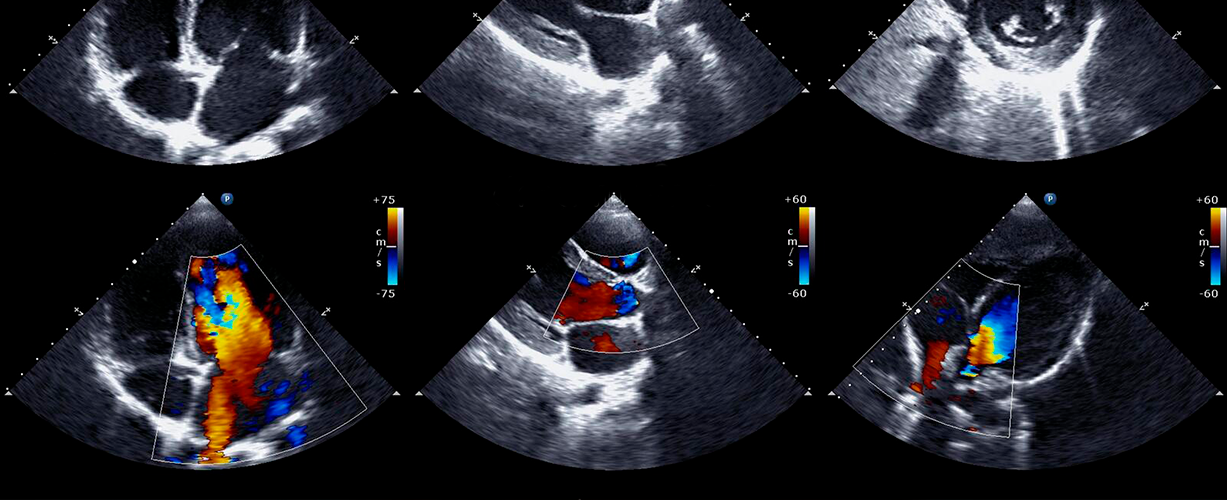

Врач может анализировать разные параметры, такие как размеры камер сердца, толщина стенок, подвижность клапанов и другие характеристики. Дополнительно цветная доплерография позволяет визуализировать направление и скорость крови в сосудах.

– Компьютер обрабатывает эхо сигналы и формирует детальное изображение сердца и смежных сосудов на экране. - Допплерография

– Врач специализированного профиля, обычно кардиолог или сонографер, анализирует полученные изображения для оценки структур сердца. Он описывает размеры камер, толщину стен, подвижность клапанов и остальные анатомические характеристики. - Доплерографический анализ

– Если была применена доплерография, врач анализирует направление и скорость крови в сосудах, что позволяет определить состояние кровообращения и идентифицировать возможные нарушения. - Сравнение с нормой